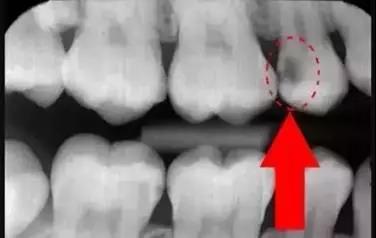

牙齒的牙根是埋在牙槽骨中的,醫(yī)生沒(méi)有透視眼,為了解患牙的牙根的形態(tài)、走向、長(zhǎng)度及根尖周有無(wú)病變及病變大小,或者懷疑有肉眼無(wú)法確認(rèn)的其它牙科問(wèn)題,都會(huì)建議患者去牙科的X光,甚至,口腔CT來(lái)全面性地確認(rèn)問(wèn)題,以訂定合適的治療計(jì)劃。

牙片(牙科X光)有助于牙醫(yī)直接觀察到普通口腔檢查難以發(fā)現(xiàn)的牙齒和牙周組織問(wèn)題,是早發(fā)現(xiàn)早治療口腔問(wèn)題的關(guān)鍵。希望大家一定要認(rèn)識(shí)到牙片的重要性,拍片醫(yī)生不是為了訛?zāi)沐X(qián),拍片沒(méi)有很大的風(fēng)險(xiǎn),大家不要擔(dān)心!